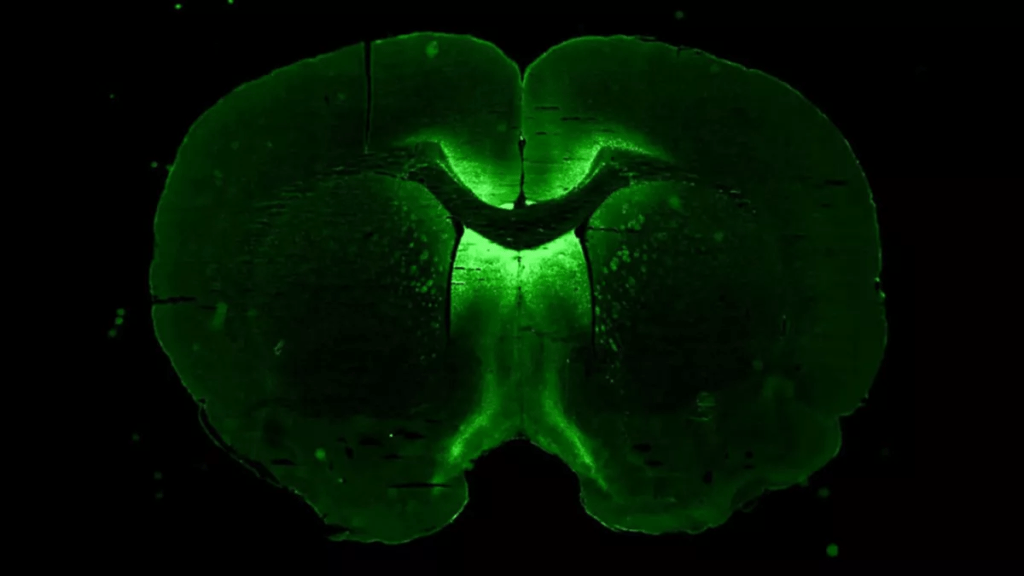

An upcoming resupply mission to the International Space Station will include stem cells destined to be grown into tiny, 3D models of the human brain.